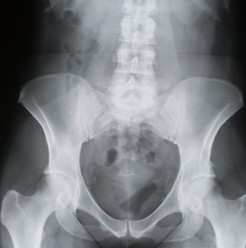

Как узнать о развитии аденомы предстательной железы

Все нарушения, обусловленные аденомой предстательной железы, связаны со сдавлением увеличенной железой уретры и проявляются следующим образом. Условно урологи делят течение болезни на 3 стадии, подробное описание которых вы дайдете в статье.

Синдром хронической тазовой боли

Синдром хронической тазовой боли — распространенное, часто хроническое состояние, характеризующееся болями в области крестца, промежности, мошонки, паха, над лобком, в пенисе. Пациенты ощущают жгучую боль при эякуляции. Либидо (влечение) ослаблено, отмечается частичная импотенция. Кроме этого, возможны дизурические явления в виде частых позывов. Симптомы синдрома хронической тазовой боли часто рецидивируют, причем обострение может длиться в течение нескольких месяцев, значительно снижая качество жизни.